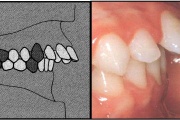

Esimese jäävmolaari ektoopiline lõikumine

Ravijärgne seis. Jäävhammas on täielikult lõikunud.

) Röntgenülesvõte. Ülemise esimese jäävmolaari lõikumine on takistatud 2. piimamolaari tõttu